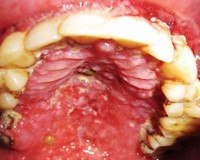

ВИЧ. Инфекция полости рта - патологические изменения органов полости рта, наблюдающиеся у инфицированных вирусом иммунодефицита пациентов. При вторичном иммунодефиците начинается активное размножение условно-патогенной и патогенной флоры. Это приводит к развитию инфекционно-воспалительных, дегенеративных и онкологических процессов в полости рта: гингивита, пародонтита, хейлита, вирусных и грибковых поражений, саркомы Капоши и тд Диагностика ВИЧ осуществляется лабораторными методами и направлена на обнаружение в крови самого вируса, антител к нему и оценку состояния клеточного звена иммунной системы. Эффективное лечение на сегодняшний день не разработано, основой терапии являются антиретровирусные препараты.

ВИЧ-инфекция полости рта - это группа стоматологических заболеваний, развивающихся одними из первых у пациентов с приобретенным иммунодефицитом. Патологические изменения полости рта у ВИЧ-инфицированных диагностируются в 30-80% случаев и позволяют не только заподозрить наличие заболевания, так и сделать выводы о его прогрессирующем течении либо неэффективности антиретровирусной терапии. От момента инфицирования ВИЧ до появления первых клинических признаков может пройти от 2-х до 5-ти лет, в течение которых пациент не предъявляет каких-либо жалоб, но при этом является потенциально опасным. Настороженность стоматологического персонала и знание клинической картины ВИЧ в полости рта позволяет диагностировать заболевание на ранних стадиях и направить пациента на специфическое лечение.

В стоматологии клинические формы ВИЧ в полости рта разделяются на 3 группы, исходя из степени предположительной связи с инфицированием. К первой группе относятся патологические процессы, наиболее тесно связанные с вирусом иммунодефицита (кандидоз, волосатая лейкоплакия, ВИЧ-гингивит, язвенно-некротический гингивит, ВИЧ-пародонтит, саркома Капоши, нон-Ходжскинская лимфома). Вторую группу составляют поражения, в меньшей степени ассоциированные с ВИЧ (атипичные язвы, идиопатическая тромбоцитопеническая пурпура, патология слюнных желез, вирусные инфекции). В обширную третью группу входят поражения, которые могут быть при ВИЧ-инфекции, но не связаны с ней.